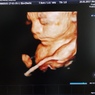

My interest in medicine began at age 12 and was instilled by my father, an Orthopedic himself. I decided to specialize in Gynecology because it covers both surgical and medical field.